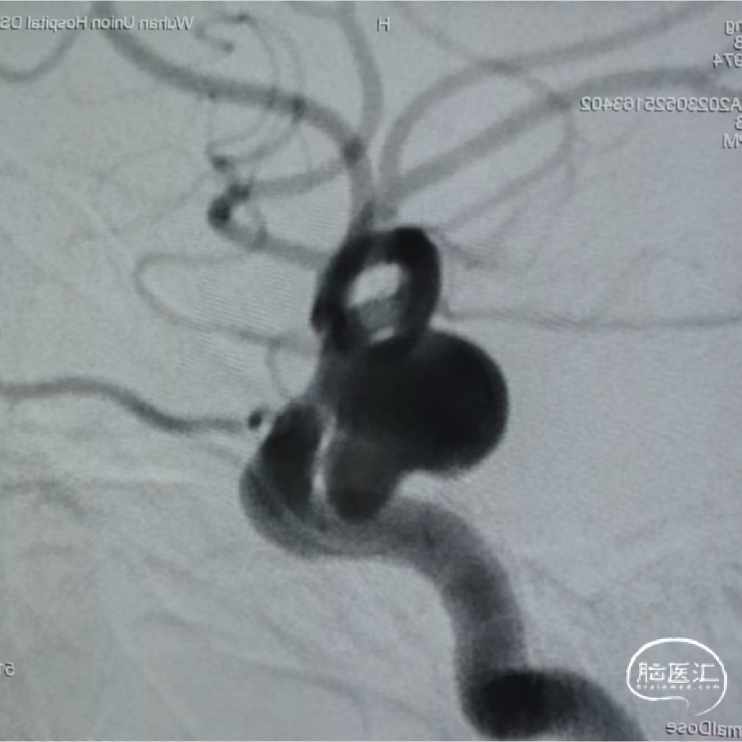

患者:女性,49岁。

主诉:右侧颈内动脉C6段动脉瘤。

动脉瘤测量:

动脉瘤大小12.9mm*9.8mm

瘤颈宽度5mm

瘤颈远端血管直径2.3mm,近端血管直径4.3mm

手术策略:植入赛诺神畅涂层血流导向密网支架 4.25mm*25mm。

术前影像